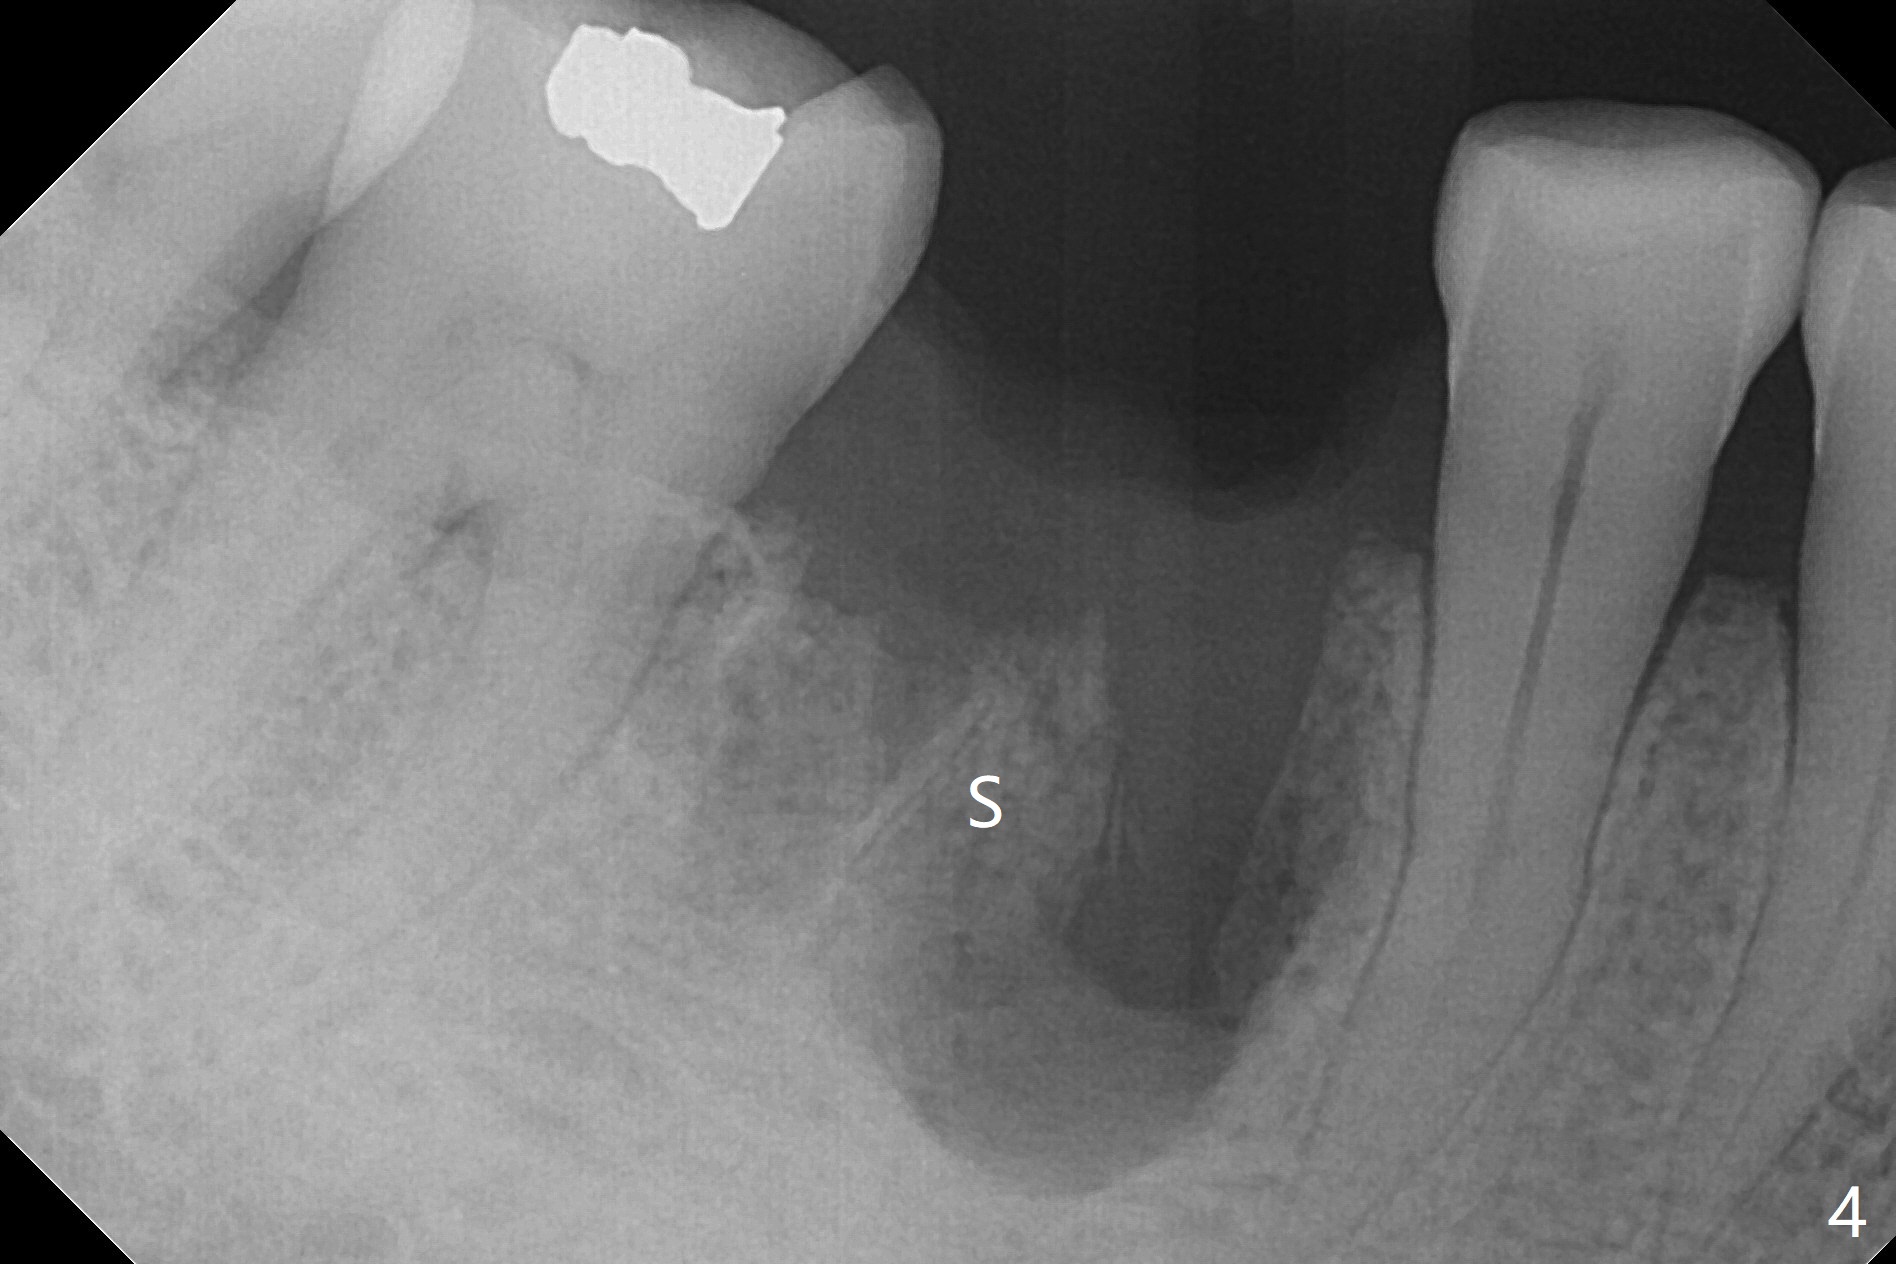

Preop oral Amoxicillin seems to be associated with reduction in the buccal and lingual (Fig.3 arrow) fistulae at #30, but there is mesiobuccal swelling (Fig.1 *) with 7 mm pocket (Fig.2). Osteotomy is initiated in the middle of the septum (Fig.3-5 S). As the osteotomy increases, it shifts mesially (Fig.6 arrow). Guided surgery is able to reduce shifting. A 5x13 mm implant is not seated completely (Fig.7) apparently due to osteotomy shifting. After removal of the bone from the osteotomy distally, the implant remains unseated with lower torque value (Fig.8). Following reuse of the 4.3 mm drill deeper by 1-2 mm, the implant is seated to a satisfactory depth (Fig.9 with increase in torque to 50 Ncm) with placement of Vera Graft (*) and a 7.5x4(3) mm abutment. After a second round of allograft placement (Fig.10 *), the implant is found to be 4 mm from the IAC. At the later stage of osteotomy, the coronal end of the septum is destroyed with loss of osteotomy depth landmark. It is apparent that the soft tissue landmark may be more reliable. The implant threads appear to be covered by the bone graft 3.5 months postop (Fig.11). The abutment is changed to 6.5x5(3) mm one before impression with minor margin prep. The bone density seems to increase 5 months postop, i.e., immediately post cementation (Fig.12) and 10 months postop (5 months post cementation (after retightening abutment), Fig.13 (*)). Periimplantitis develops mesiobuccally, consistent with bone loss 1 year 7 months post cementation (Fig.14 *); the implant seems to have been buccally placed. Bone graft is necessary with PRF or GEM21S if the vein is small and 6-month membrane with a hole around a 7.5x4(4) cemented abutment for easy wound closure. Take 5x5 CM CBCT to determine which wall has defect, buccal or lingual. Check mesial contact. If so, remove the crown, reseat the abutment (possible incomplete seating) and re-impress after bone graft.